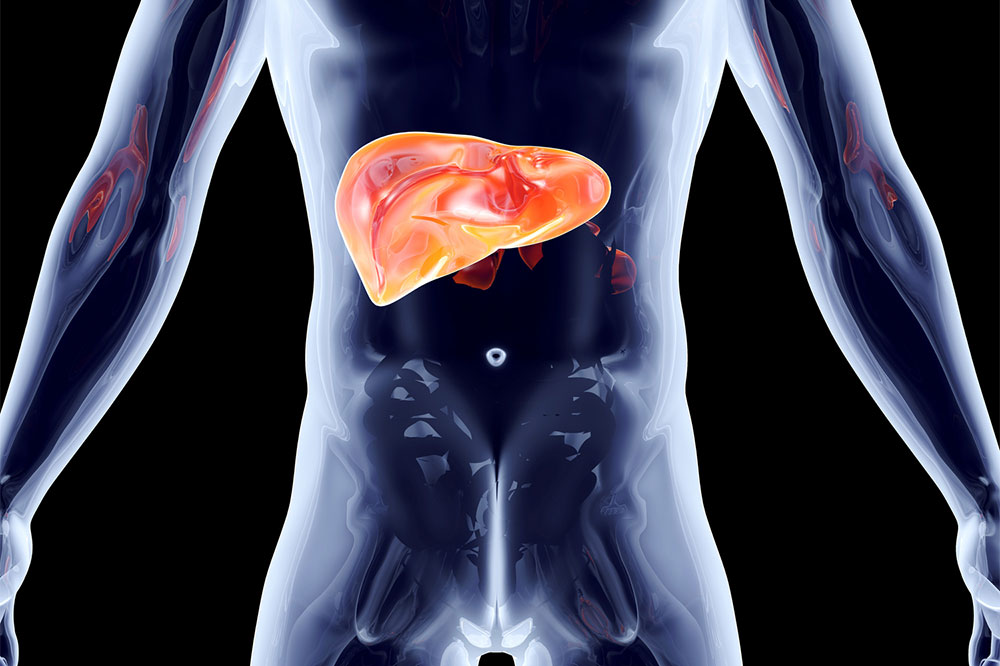

Considered the second-largest organ in the body, the liver plays an extremely important role in a variety of functions. It is key to the body’s metabolism; and helps burn fat and maintain body weight. It is located above the stomach and beneath the diaphragm, its size similar to that of a football. While such information is common knowledge, there are a few not-so-known facts about this organ. Read on to find out more: